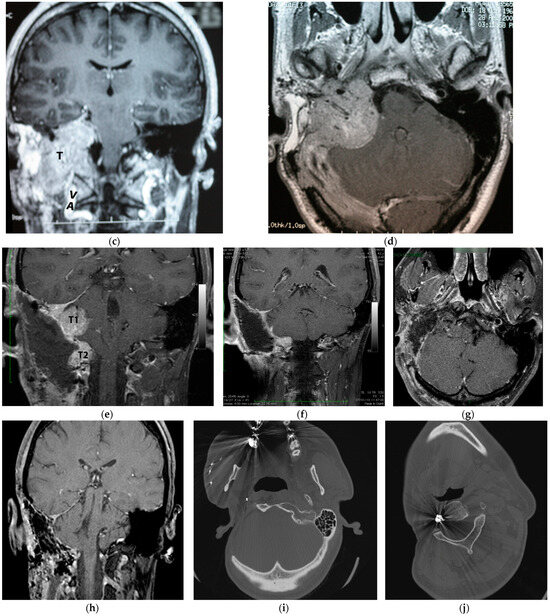

5.2. Case 2: (C3Di1 + Stage I VP)

5.3. Case 3: (C4Di2Vi)

5.4. Case 4: (C3Di2 + Stage II Vagal PGL)

5.5. Case 5: (C3Di2Vi)

5.6. Case 6: (C4Di2Vi)